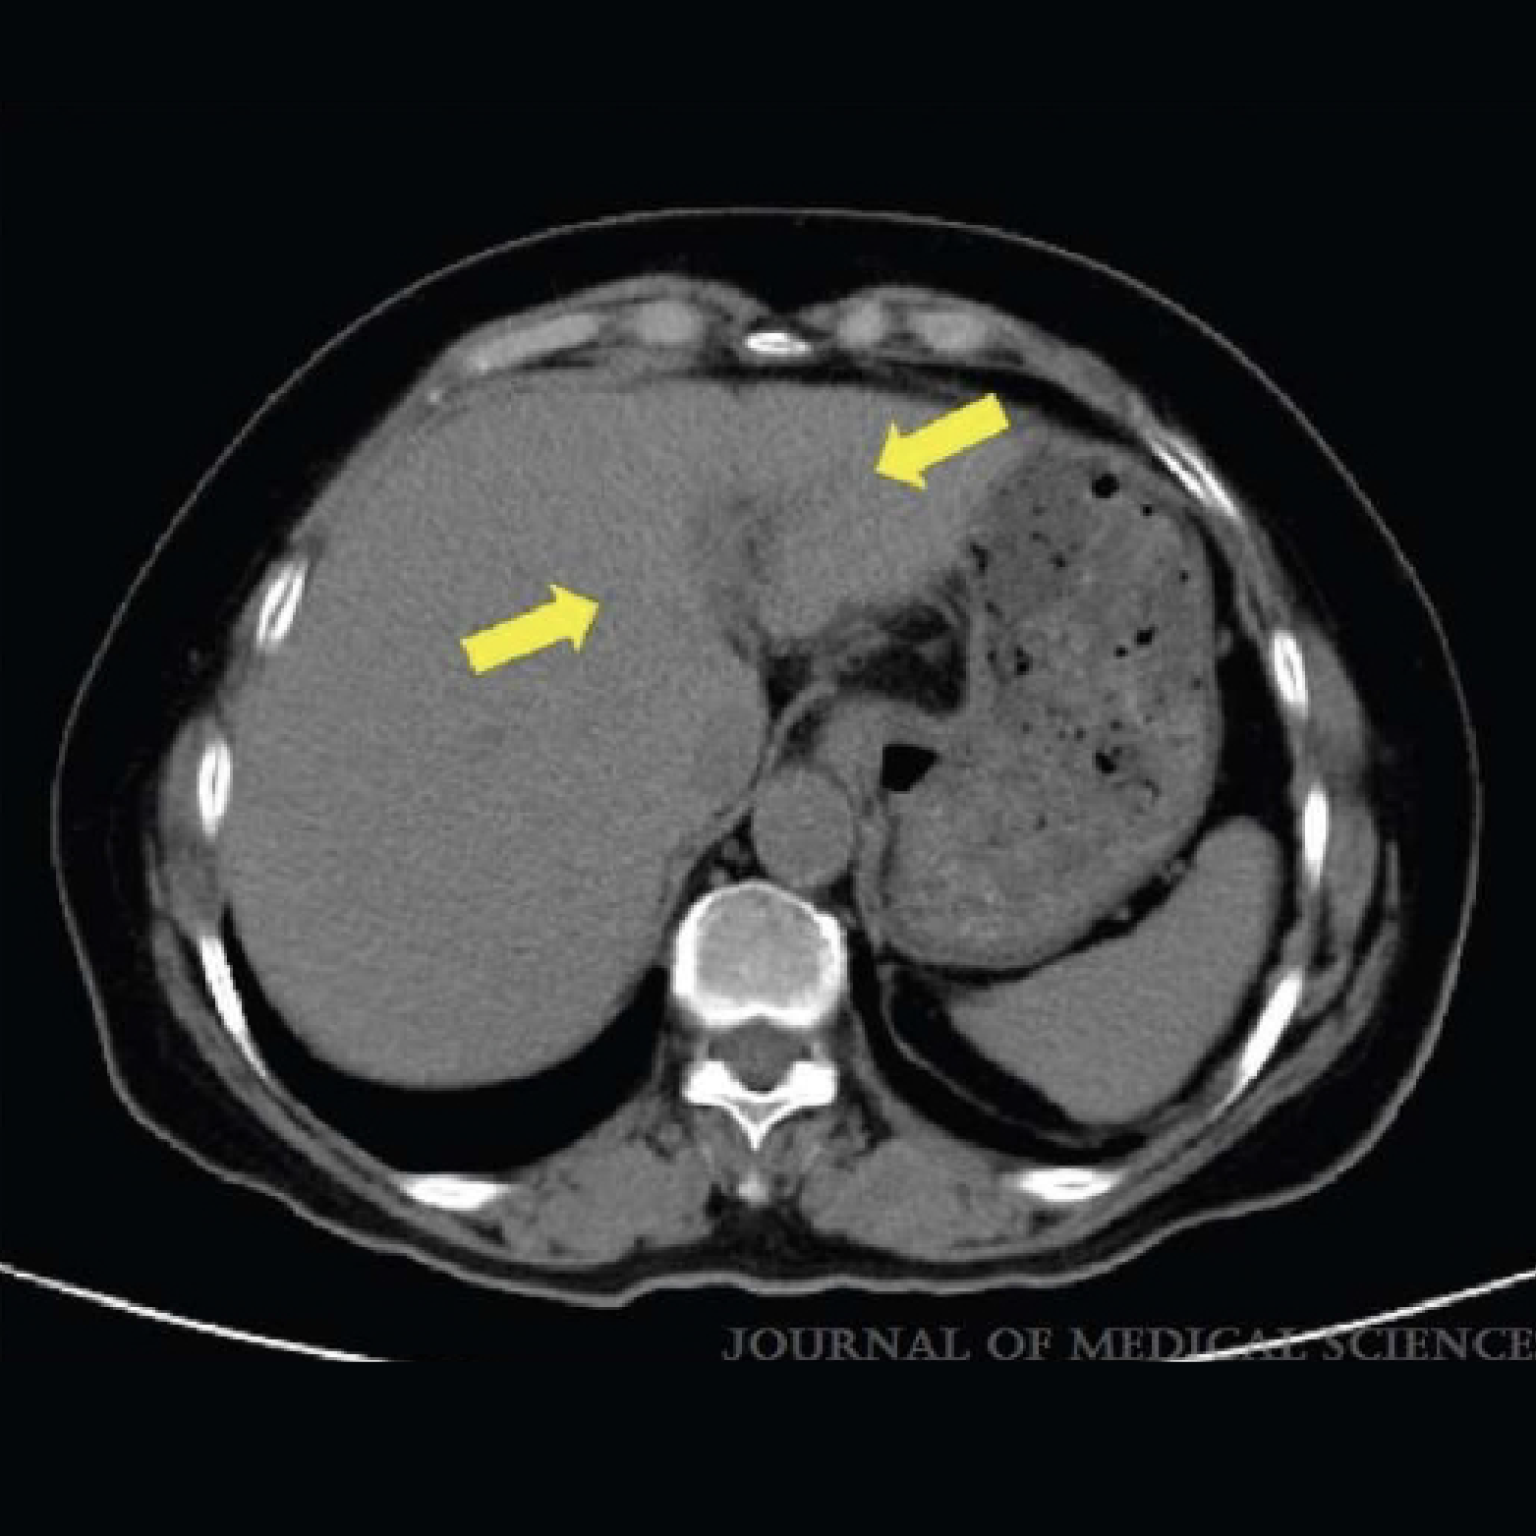

完成(IKC®)治療3個月後 未發現可辨識的肝腫瘤。

這份病例報告描述了在24週的自體免疫殺手細胞(IKC®)治療後,成功治療了源自肺腺癌的轉移性肝腫瘤。本研究已獲得三軍總醫院、國防醫學院的批准。

批准號碼:B202005066|批准日期:2020/05/13